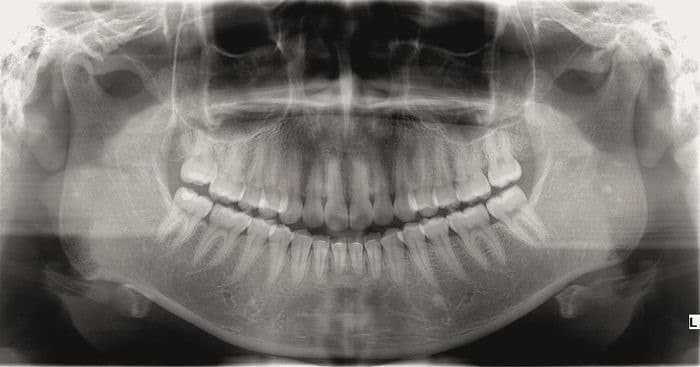

فقد تصبح حشوات الأسنان بلا أي قيمة عما قريب، وذلك بعد الكشف مؤخراً عن دواء يسمى تايديجلوسيب (Tideglusib) -وهو دواء تم تطويره خصيصاً لعلاج مرض الزهايمر-، حيث وجد العلماء أن هذا الدواء قد نجح في تعزيز النمو الطبيعي للأسنان، مما يعطي الفرصة لملء تجاويف الأسنان بصورة طبيعية. وقد نشرت الدراسة في مجلة scientific reports.

ويعمل تايديجلوسيب عن طريق تحفيز الخلايا الجذعية في اللب الداخلي للأسنان، والتي تعمل كمصدر للعاج الجديد.

ويمثل العاج (dentin) المادة المعدنية المتواجدة تحت مينا الأسنان، والتي تتآكل في حالة حدوث تسوس الأسنان، ويمكن للأسنان أن تقوم بتجديد العاج الخاص بها بشكل طبيعي ومن دون مساعدة، ولكن هذا يحدث فقط في ظل ظروف معينة.

فعند تعرض اللب الداخلي للعدوى (كالتسوس)، تقوم الأسنان بتصنيع العاج، ولكن الأسنان تحت الظروف الطبيعية يمكنها إنتاج طبقة رقيقة جداً من العاج لا تكفي لإصلاح التجاويف العميقة الناتجة عن إصابتها بالتسوس، وهنا يأتي دور تايديجلوسيب حيث يعمل عن طريق تعطيل عمل الإنزيم GSK-3، وهو الإنزيم الذي يوقف عملية تصنيع العاج.

ولإثبات ذلك قام الفريق البحثي بإدخال قطع إسفنجية صغيرة قابلة للتحلل، مصنوعة من الكولاجين ومحملة بـ تايديجلوسيب إلى تجاويف الأسنان، وقد وجدوا أن تلك القطع الإسفنجية قد حفزت نمو العاج بشكل هائل، حيث تم إصلاح التجاويف طبيعياً خلال ستة أسابيع فقط، وذلك قبل أن تتحلل كلياً تاركةً الأسنان سليمة.